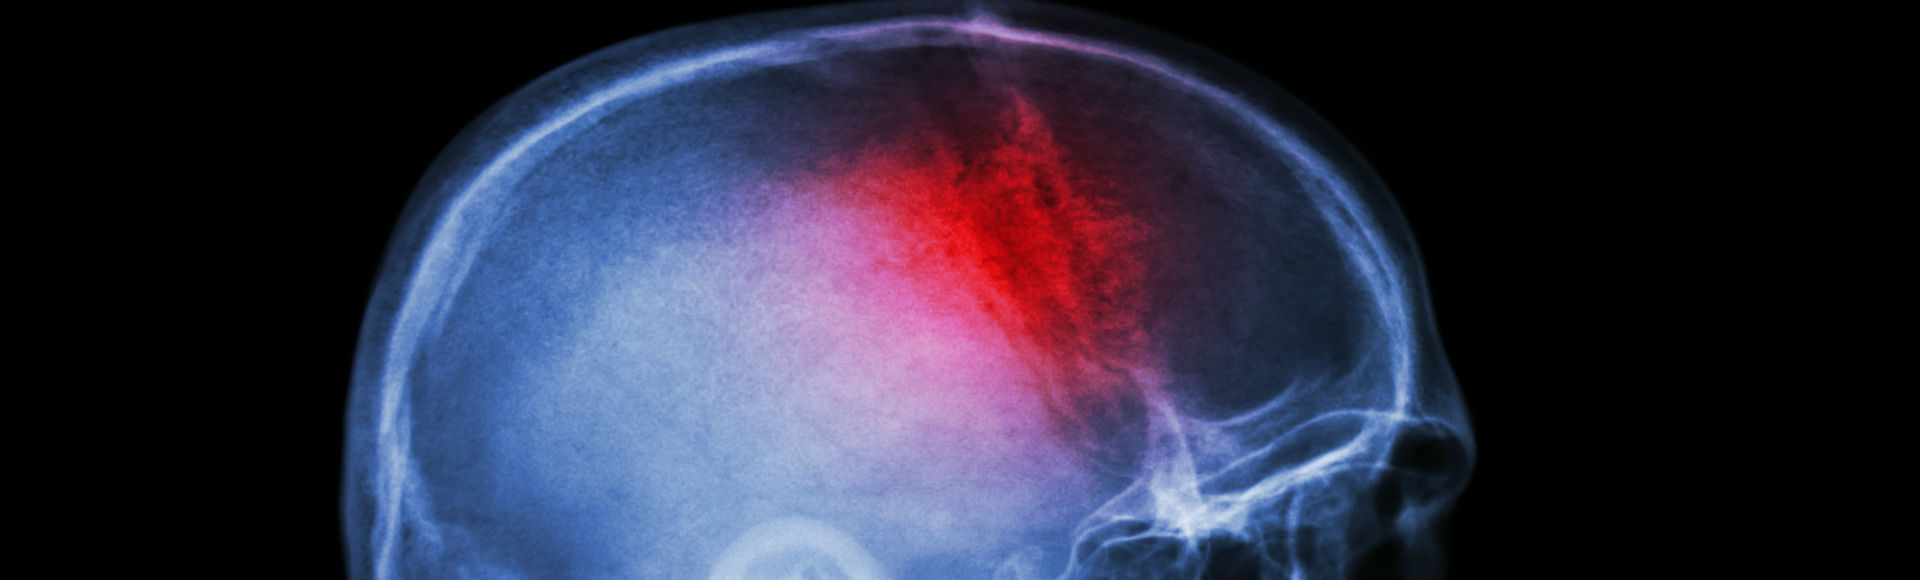

Stroke is a serious, life-threatening and often debilitating condition which can have a devastating impact on patients and their families. In the UK, nearly 95,000 people are admitted to hospital following a stroke each year. Many stroke survivors are left severely disabled.

New research led by Dr Peter McMeekin, from Northumbria University, shows that one in 10 stroke patients admitted to hospital each year could benefit from a revolutionary treatment called a ‘mechanical thrombectomy’.

While many people with a stroke caused by a clot currently get drugs to help dissolve the blockage, this does not always work completely. Thrombectomy - or clot retrieval - is a method, which aims to remove the clot mechanically.  Mechanical thrombectomy delivered alongside existing clot busting drugs more than doubles the numbers of stroke patients who remain independent. It is a time critical highly skilled operation, and stroke services need to be set up to be able to deliver the treatment.

A thin metal wire housing a mesh is inserted into a major artery in the leg and, under X-ray guidance; it is directed to the site of the problem in the brain. The mesh is then expanded to trap and remove the clot.